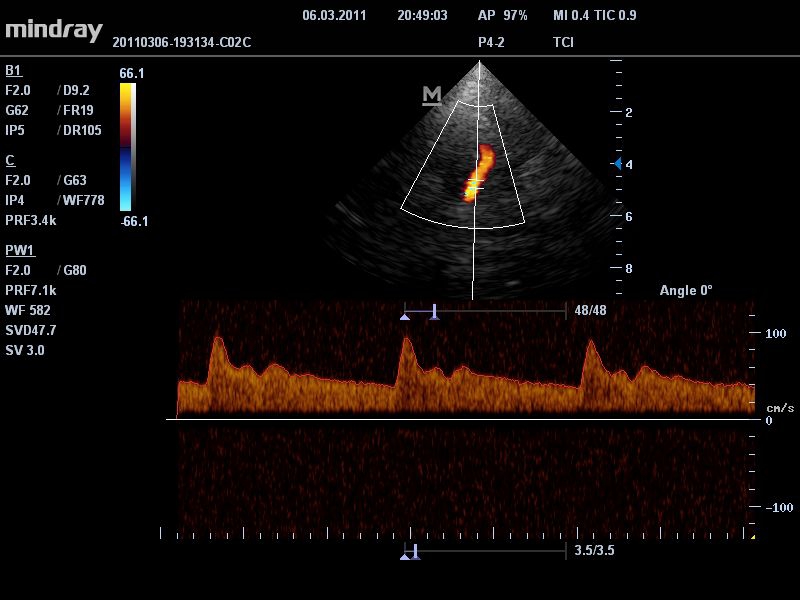

Mindray DC-T6

Ультразвуковая система Mindray DC-T6 – это инновационный аппарат для проведения высокого уровня диагностики с качественной визуализацией и широким спектром применения. Платформа рекомендована для использования в коммерчески многопрофильных медицинских учреждениях и государственных лечебных клиниках.

• Режимы сканирования: B/M/CFM/PDI/Направленный PDI/PW, HPRF, Тканевая гармоника, М- и цветной М-режим.